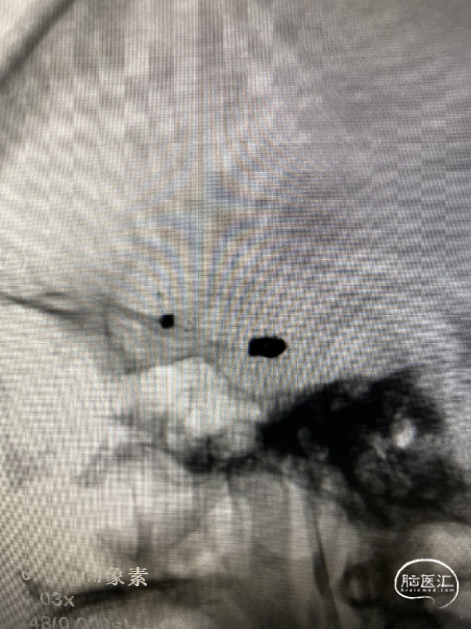

造影:左侧颈内动脉交通段动脉瘤支架辅助栓塞后改变,瘤体内无造影剂泻入,大脑中动脉及大脑前动脉走形正常,显影良好,左侧大脑前动脉A3段可见约2.0mm*1.5mm大小动脉瘤。右侧颈内动脉交通段可见约6.7mm*2.8mm大小动脉瘤,分叶状,瘤颈宽4.0mm,胚胎型大脑后动脉,右侧大脑中动脉M1段可见宽颈梭型动脉瘤,大小约3.9mm×4.6mm。

右侧颈内动脉交通段可见约6.7mm*2.8mm大小动脉瘤,分叶状,瘤颈宽4.0mm

右侧大脑中动脉M1段可见宽颈梭型动脉瘤,大小约3.9mm×4.6mm,左侧大脑前动脉A3段可见约2.0mm*1.5mm大小动脉瘤。